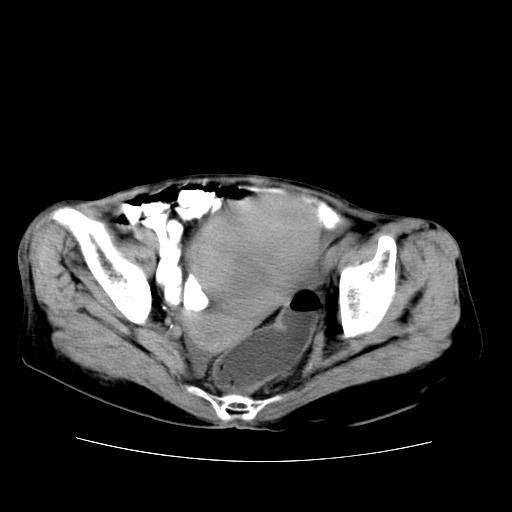

女性,72岁。

主诉下腹部坠痛不适1年余。

子宫增大如孕3月大小,质软,活动可,无压痛。

b超提示:盆腔(子宫前方)低回声团块。

临床诊断:盆腔肿块查。

1、这个肿瘤密度均匀,增强后轻中度均匀性强化,与左侧附件关系密切,肿瘤边缘光整、清晰。

2、左侧卵巢增大呈8×8×10cm大小,实性,表面光滑,边清,左侧输卵管爬行于左卵巢上,子宫萎缩。右输卵管、卵巢萎缩。

3、病理号:092658

左侧卵巢纤维瘤(性索间质肿瘤)

卵巢纤维瘤为良性卵巢性索间质肿瘤,常为单侧发病,当合并腹水或胸腹水时称麦格斯(meigs)综合征,肿瘤切除后胸腹水可消失。ct表现为盆腔内边界清楚的圆形或椭圆形肿块,常有分叶或不规则;肿瘤多为实性,少数为囊性、囊实性,完全囊性者可见壁结节。实性部分与子宫等密度;增强扫描常为轻度强化或几乎不强化。